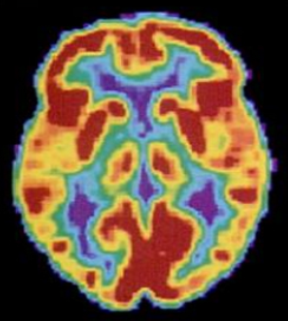

Positron emission tomography (PET) scans create pictures of the living, active brain (Figure 3.30). An individual receiving a PET scan drinks or is injected with a mildly radioactive substance, called a tracer. Once in the bloodstream, the amount of tracer in any given region of the brain can be monitored. As a brain area becomes more active, more blood flows to that area. A computer monitors the movement of the tracer and creates a rough map of active and inactive areas of the brain during a given behavior. PET scans show little detail, are unable to pinpoint events precisely in time, and require that the brain be exposed to radiation; therefore, this technique has been replaced by the fMRI as an alternative diagnostic tool. However, combined with CT, PET technology is still being used in certain contexts. For example, CT/PET scans allow better imaging of the activity of neurotransmitter receptors and open new avenues in schizophrenia research. In this hybrid CT/PET technology, CT contributes clear images of brain structures, while PET shows the brain’s activity.

A brain scan shows different parts of the brain in different colors.

Figure 3.30 A PET scan is helpful for showing activity in different parts of the brain. (credit: Health and Human Services Department, National Institutes of Health)